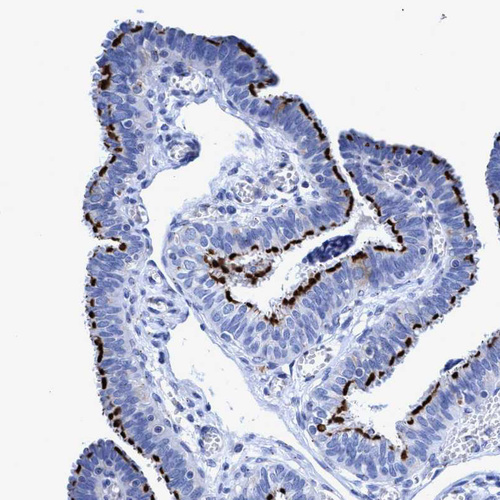

Immunohistochemistry analysis in human fallopian tube and liver tissues using HPA021191 antibody. Corresponding CROCC RNA-seq data are presented for the same tissues.